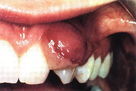

臨床上有3%-10%的孕婦會患妊娠性牙齦瘤,表現為牙齦乳頭呈球狀增生,嚴重時甚至能把整個牙齒都覆蓋住,有出血現象,還會妨礙進食或發生感染,影響胎兒的健康。這種疾病在懷孕3-9個月最多見。

臨床上一般出現滿口牙都被覆蓋住的情形比較少,多是一個或多個牙齒被覆蓋,一般不需要特別治療,一般分娩後可自行消退,只要診斷清楚即可。如果牙肉腫大,範圍很廣,可能要做手術切除。